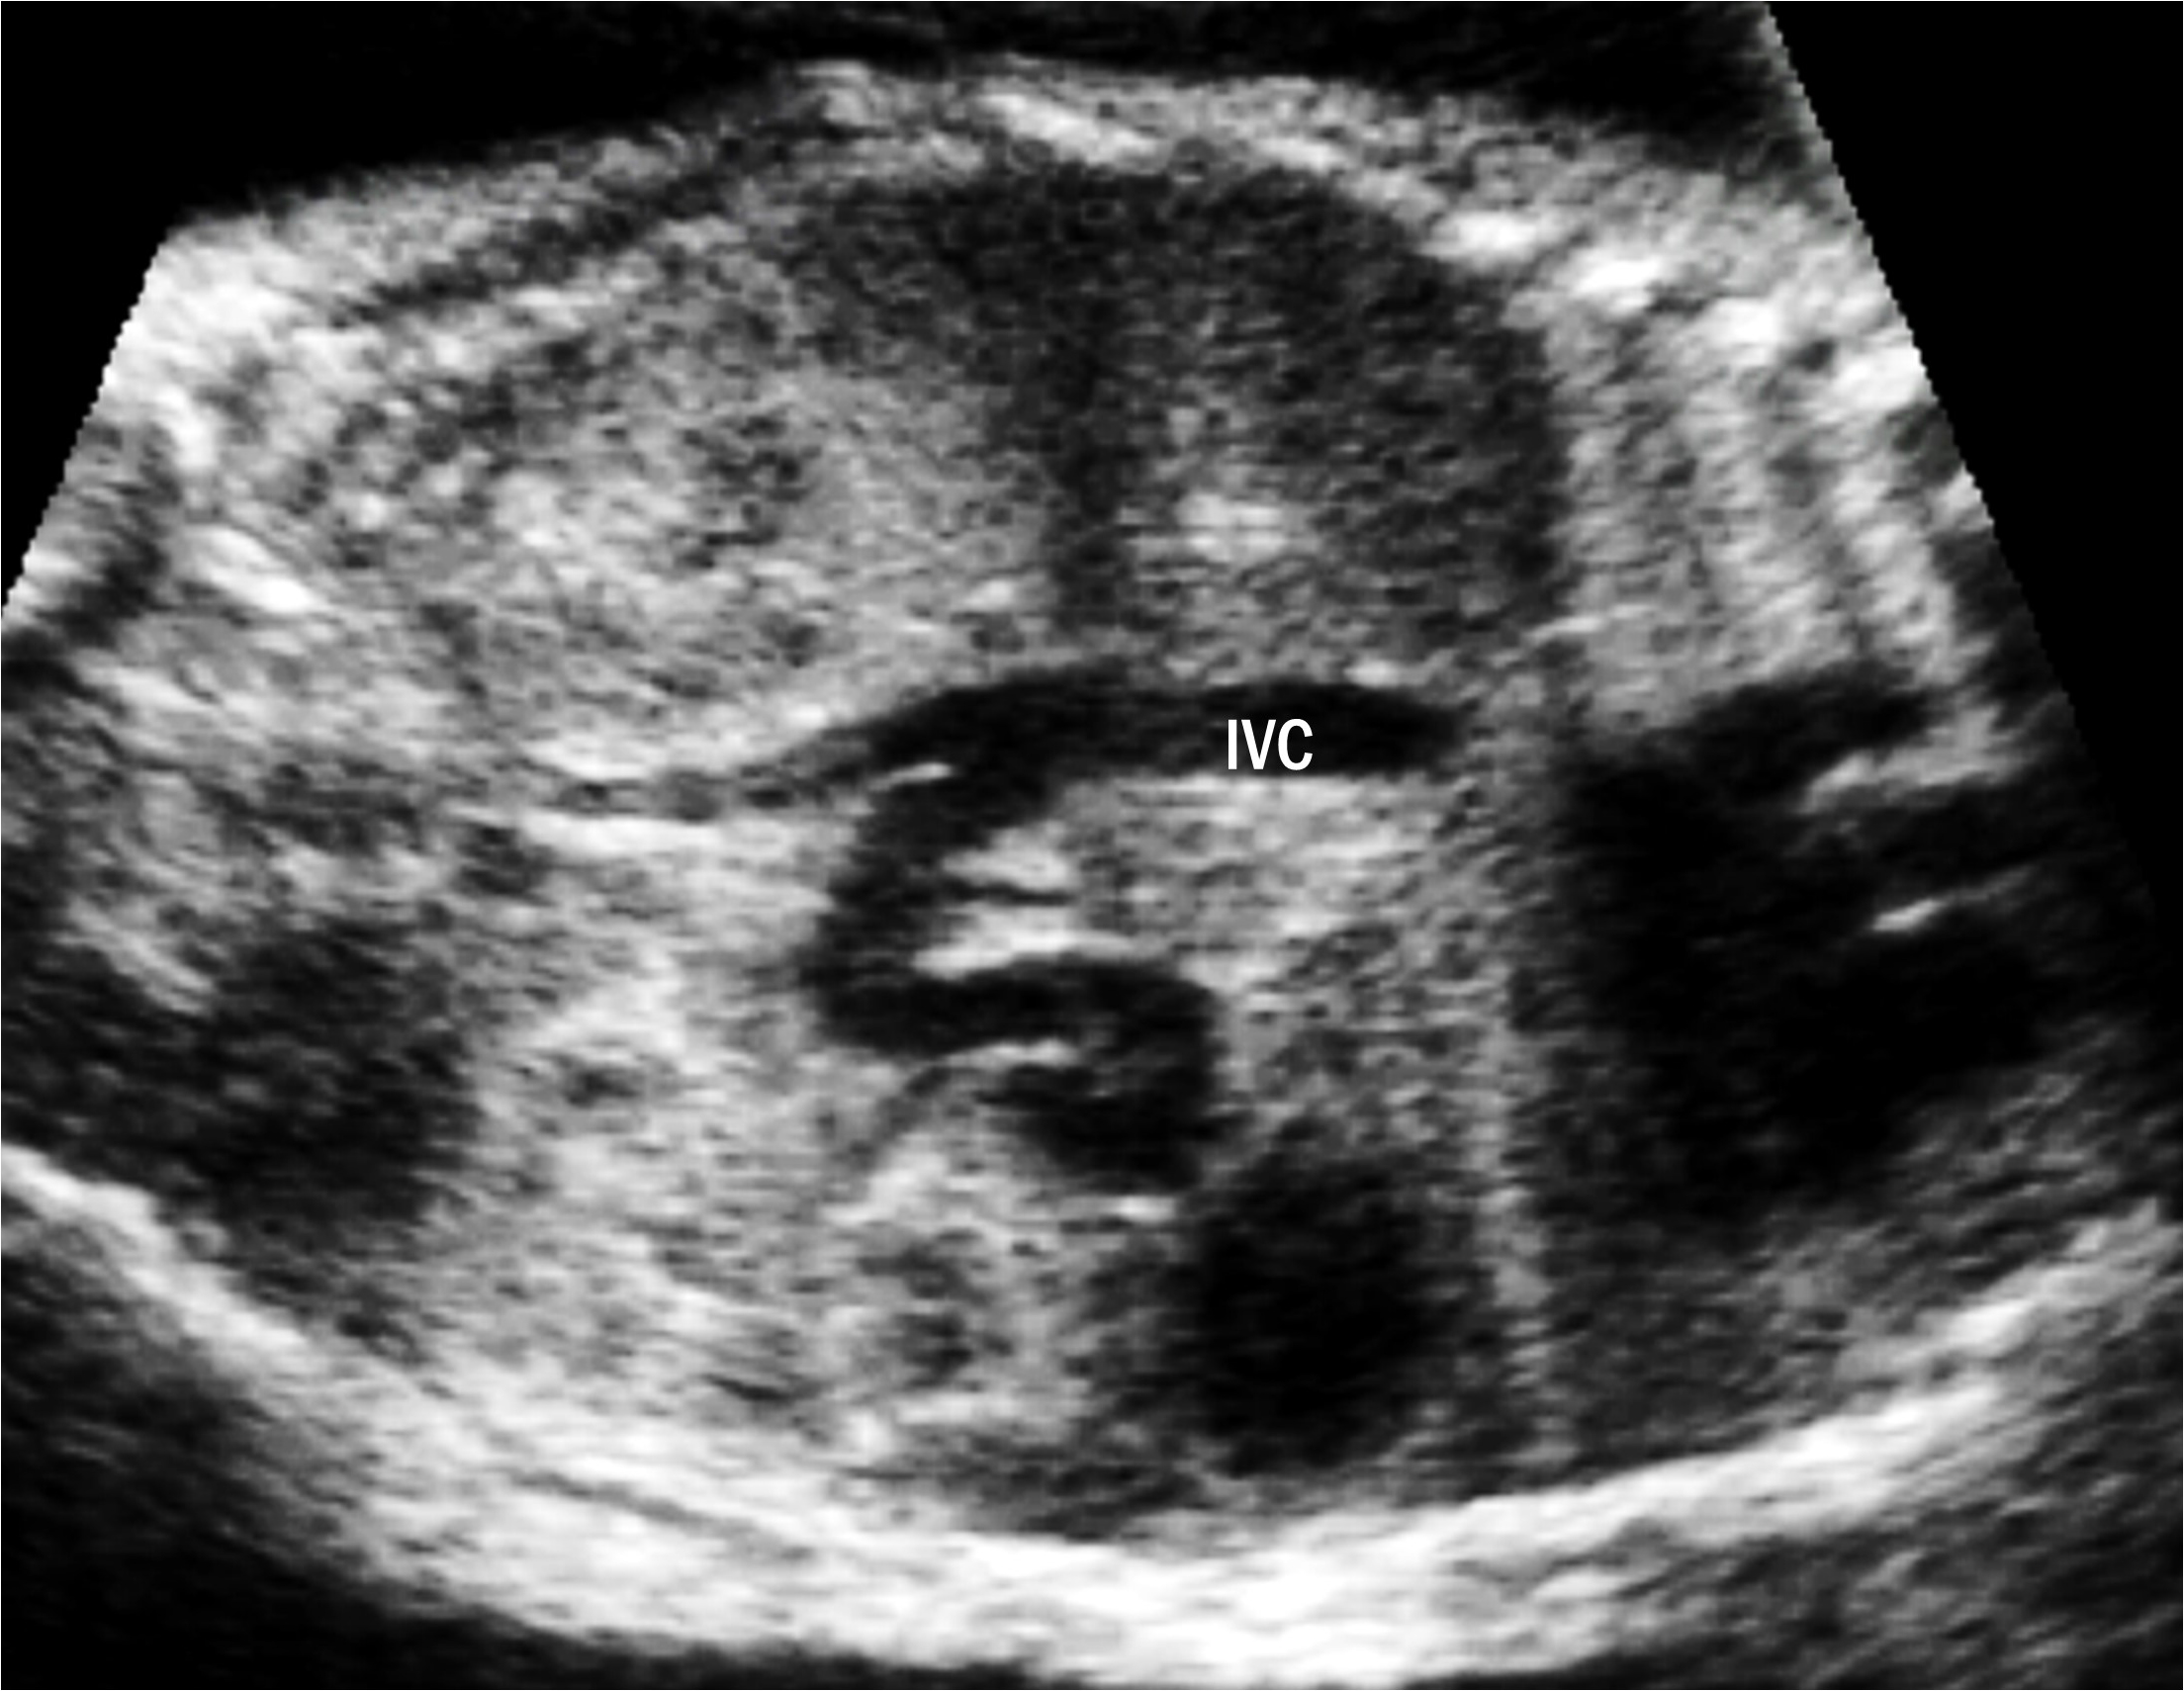

We found one case of type II UPSVS (case 9). The fetus had a short DV that drained into the IVC, but other structures of the umbilical-portal-DV complex were intact. The fetus showed cardiomegaly and fetal hydrops with severe skin edema and pleural effusion (Fig. 3). This fetus was confirmed to have a 3p deletion. The fetal hydrops resolved after birth. At the time of writing, the patient was 17 months old and had developmental delay.

Fig. 3.Ultrasound images of type II umbilical-portal-systemic venous shunt in case 9. The fetus showed severe fetal hydrops: (a) severe skin edema and (b) pleural effusion. (c) Transverse abdominal image shows the UV connected to the DV and it drains at the lower site than usual. (d) Sagittal image shows a short DV draining into the IVC below the diaphragm. UV, umbilical vein; DV, ductus venosus; IVC, inferior vena cava; RA, right atrium.